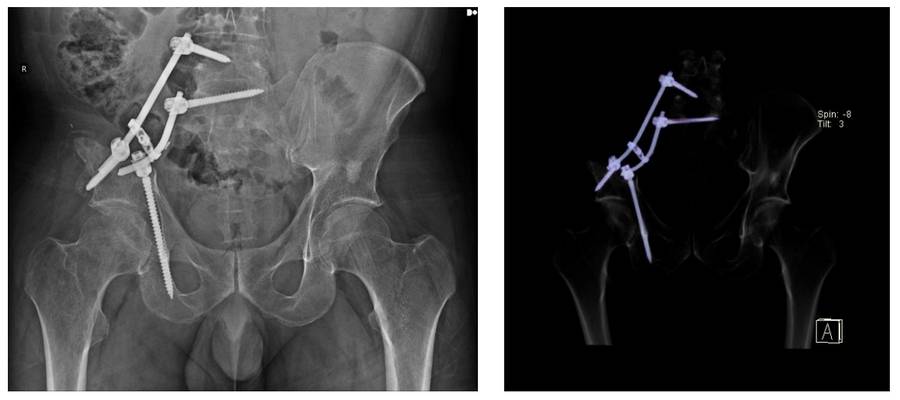

Postoperative: The image shows fixation with rods and screws after sacroiliac resection.